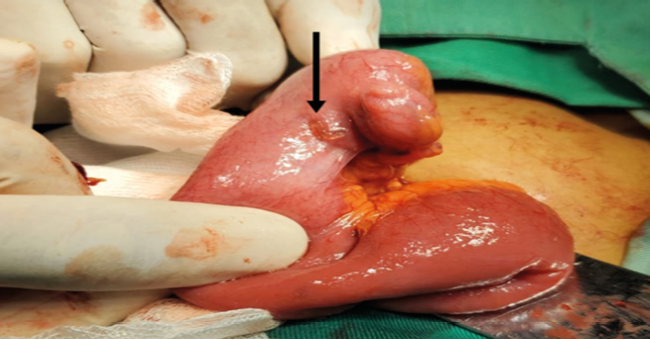

Figura 1

Divertículo de Meckel observado en caso1

Nota: La flecha en la figura muestra divertículo de Meckel observado en el paciente del caso 1.

Fuente: Archivo de imágenes capturadas durante procedimiento en sala de operaciones

Se preparó al paciente para su intervención de urgencia en sala de operaciones, con diagnóstico prequirúrgico de apendicitis aguda no complicada. La intervención quirúrgica, clasificada como cirugía clase II, fue realizada el 20/02/23 por el Cirujano Dr. Mejía (Médico de Base), con el primer ayudante Dr. Hernández (Residente de tercer año) y el segundo ayudante Dr. González (Residente de segundo año). Se procedió a administrar anestesia regional (Bupivacaina pesada al 0.5%, 15 ml administrada en el espacio epidural a nivel de la región lumbar) y sedación preoperatoria (Midazolam, dosis inicial:3ml por vía intravenosa y dosis de mantenimiento 3ml cada hora) por la médica especialista en anestesiología Dra. Martínez, quien realizó el bloqueo espinal. La intervención duró una hora y diez minutos [Inicio 2:30 pm - Fin 3:40 pm]. El paciente, en posición de decúbito supino, fue sometido a una apendicetomía por vía convencional mediante incisión de McBurney. Los hallazgos transoperatorios (Cuadro 1) confirmaron el diagnóstico prequirúrgico de apendicitis aguda, corroborando que la enfermedad se encontraba en fase supurada, siendo esta la causa del abdomen agudo. De manera incidental, se encontró un divertículo de Meckel solitario, localizado a 80 cm de la válvula ileocecal, de 2x2 cm. No se observó perforación, ulceración en la mucosa del íleo, reacción inflamatoria ni bandas fibrosas que obstruyeran la luz intestinal (Figura 1). Se realizó una diverticulectomía mediante la técnica de resección en cuña con anastomosis primaria. Se enviaron ambos especímenes (apéndice vermiforme y divertículo de Meckel) al departamento de patología para su análisis histopatológico. La evolución transoperatoria del paciente ocurrió sin ninguna eventualidad, finalizando la intervención de manera exitosa.